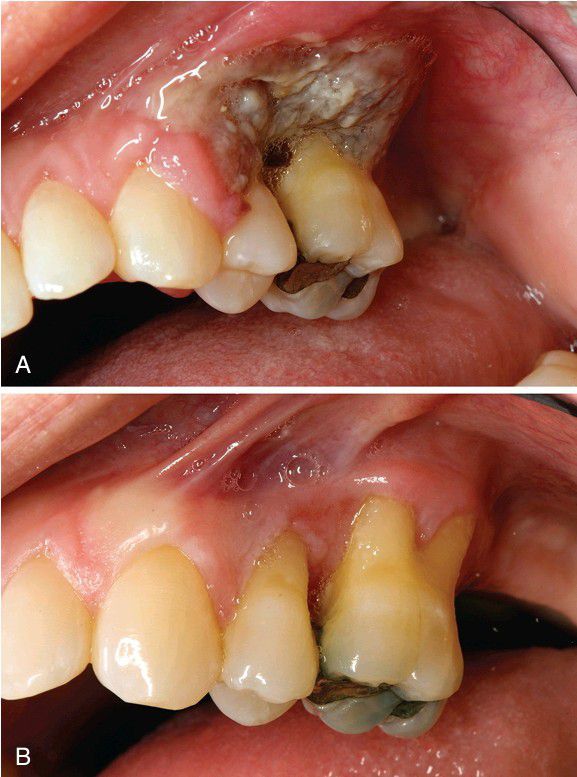

A, This 42-year-old woman, treated for autoimmune hepatitis with mycophenolate mofetil, developed painful gingival ulcers. B, Resolution of the lesion after immune suppression was stopped and rituximab therapy was initiated.